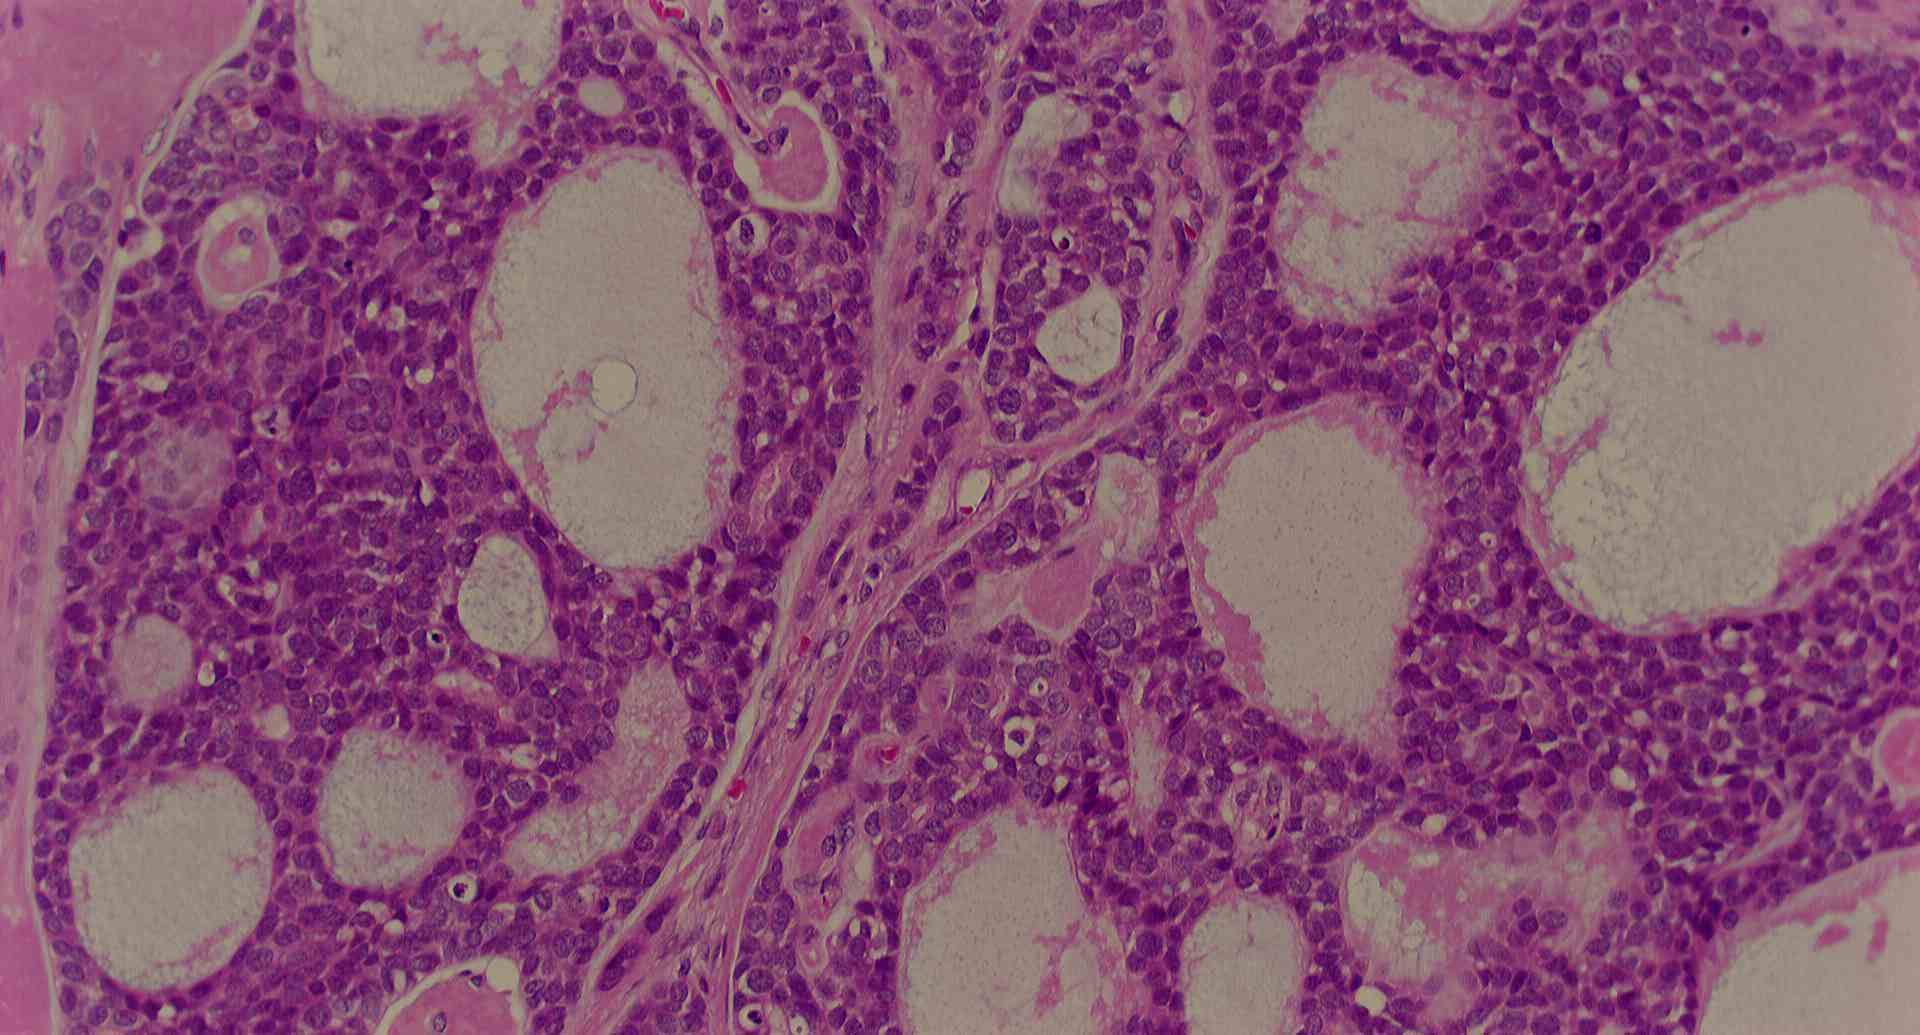

標本の説明

標本16